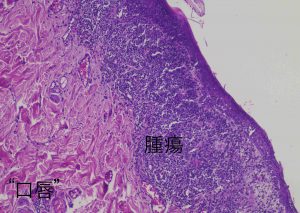

麻酔を掛けて口腔内を見ると可哀想にびらんや潰瘍があり、痛そうで可哀想でした。これは食べたく無いでしょう。

口唇は歯肉炎もあるので慎重に場所を選びます。

ただの炎症だと良かったのですが、予想通り「上皮向性リンパ腫」でした。これは表皮に限定して増殖するリンパ腫です。そうすると命には影響が少なそうなのですが、大多数のヒトの上皮向性リンパ腫と違って、犬は非常に予後が悪いです。これはヒトでは非常に悪性なグループに分類されるタイプが犬の主流のタイプだからです。